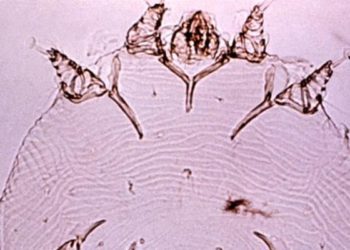

Mass Drug Administration for Scabies Control in a Population with Endemic Disease Scabies is an underrecognized and common disease ...